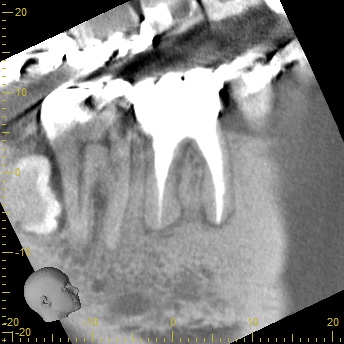

「CT」による可視化治療

画像

根管は狭く、複雑な形をしています。根管は歯の中にあるので、肉眼では見えません。根管の形を確認するためにはX線検査が必要です。

多くの歯科医院では、2次元の「レントゲン」を使って診察しますが、当院では「CT」を使います。「CT」は、お口のまわりを360度回転しながら撮影するので、立体的で鮮明な影像が得られます。

次の画像をご覧ください。これは、CTとレントゲンで同じ患部を撮影した画像です。

左の画像がCT、右がレントゲンで撮影したものです。

左の写真の赤丸で囲んだところは黒い影が映っています。これは「炎症」を示しています。一方、右の写真には黒い影はありません。つまり、レントゲンだけを使って診断すると、この炎症には気付かないということです。放置している間にこの炎症は悪化し、抜歯となってしまうかもしれません。

CTの鮮明な影像によって、正確な診断が可能になります。